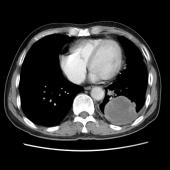

[影像描述]

左肺下叶可见高密度肿块影,边界清晰,边缘不规则,左肺下叶支气管局部截断,增强后病灶边缘轻度强化,中心未见明显强化;左侧胸腔内可见液性密度影;纵隔内未见明确肿大淋巴结影。

(左下叶)肺肉瘤样癌(巨细胞癌),伴大片坏死

肺肉瘤样癌是一种少见的非小细胞肺癌,WHO将其分为5个亚型:多形性癌、梭形细胞癌、具巨细胞癌、癌肉瘤和肺肉瘤。主要见于老年患者,男多于女,临床症状与肿瘤生长部位及侵犯周围组织的情况有关,中央型较易侵犯支气管,症状往往出现较早。CT多表现为肺内单发肿块影,最大径一般大于5cm,周围型多于中央型,可跨叶生长;边缘光滑或清晰;毛刺征及胸膜牵拉症少见;坏死、空腔及分叶、支气管截断多见,坏死边界不清,可见坏死内强化灶,肺门及纵隔淋巴结转移多为环形强化。需要鉴别以下几种疾病:肺结核球呈圆形或类圆形,多数密度不均匀,周边或中央常可见钙化,病灶中心有时可见小空洞。病灶边缘清楚,部分边缘可呈浅分叶状,少数可见毛刺征或胸膜凹陷征,周围常可见卫星灶。增强检查病灶不强化或仅轻度强化。周围型错构瘤直径多在2.5cm以下,瘤体内可见斑点状或爆米花状钙化,部分病变有脂肪密度,多数病变边缘清楚、光滑,CT增强大多数病灶无明显强化。肺炎性假瘤呈圆形或类圆形高密度影,密度较均匀,边缘多清楚而光滑,少数可呈毛刺样改变,增强检查大多数肿块较显著均匀强化。